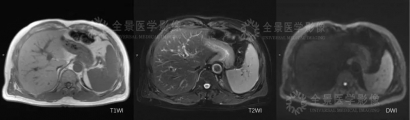

petmr检查显示:膀胱癌根治术后,术区未见异常;肝左内叶可见一类圆形结节,边界部分不清,直径约1.5cm,T1WI呈稍低信号,T2WI呈稍高信号,DWI呈稍高信号,FDG摄取轻度增高,SUVmax=3.4,肝内外胆管未见明显扩张。

mr影像图

MR软组织分辨率高,对病灶形态细节显示更为清晰,功能序列丰富,结合PET提供的代谢信息,可以为临床提供详实的影像学诊断依据。

影像医生综合考虑膀胱癌好发转移多发生于淋巴结转移、骨转移等,肝转移较为少见;从影像表现来看该病灶T2信号偏低,并不属于典型转移瘤表现,结合FDG摄取情况,倾向考虑为良性或感染性病灶,建议治疗后短期复查。